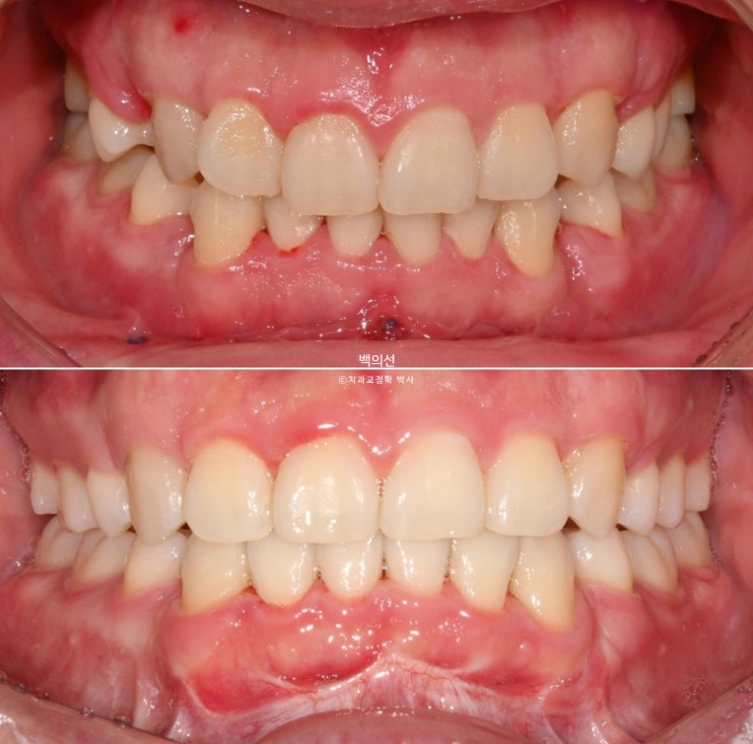

전 후 비교 보겠습니다.

24.10~25.08

남아있던 공간은 추가장치로 깔끔히 없어졌습니다.

이제 전 후 비교 보겠습니다.

총 치료기간은 10개월, 재제작 1회 입니다.

앞니가 깊게 물리는 과개교합도 좋아졌습니다.